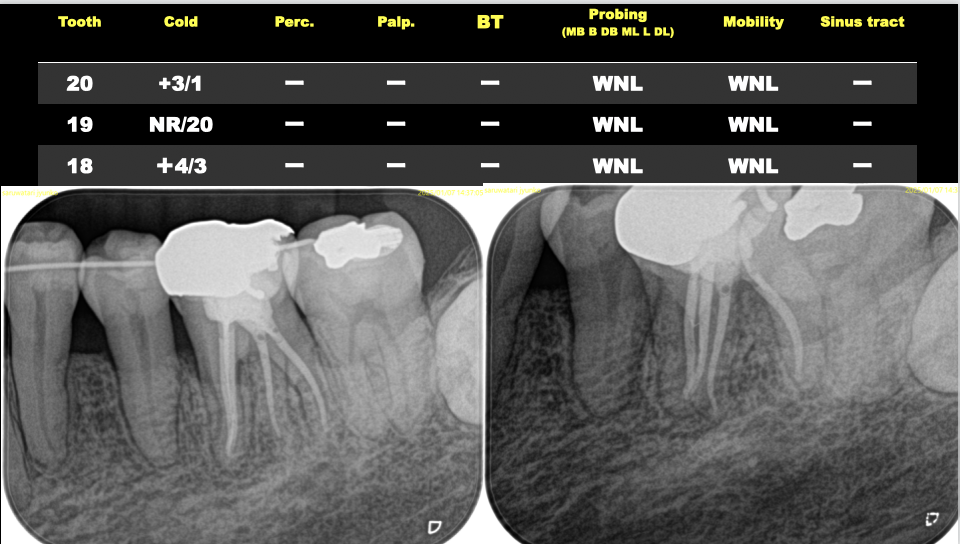

そして最後にケースを提示した。

結論的に言えば、

GatesやPessoではなく、SXを使用しメタルポストコアを避けることが肝要だろう。

さすれば歯根が割れるという悲劇は避けられる。